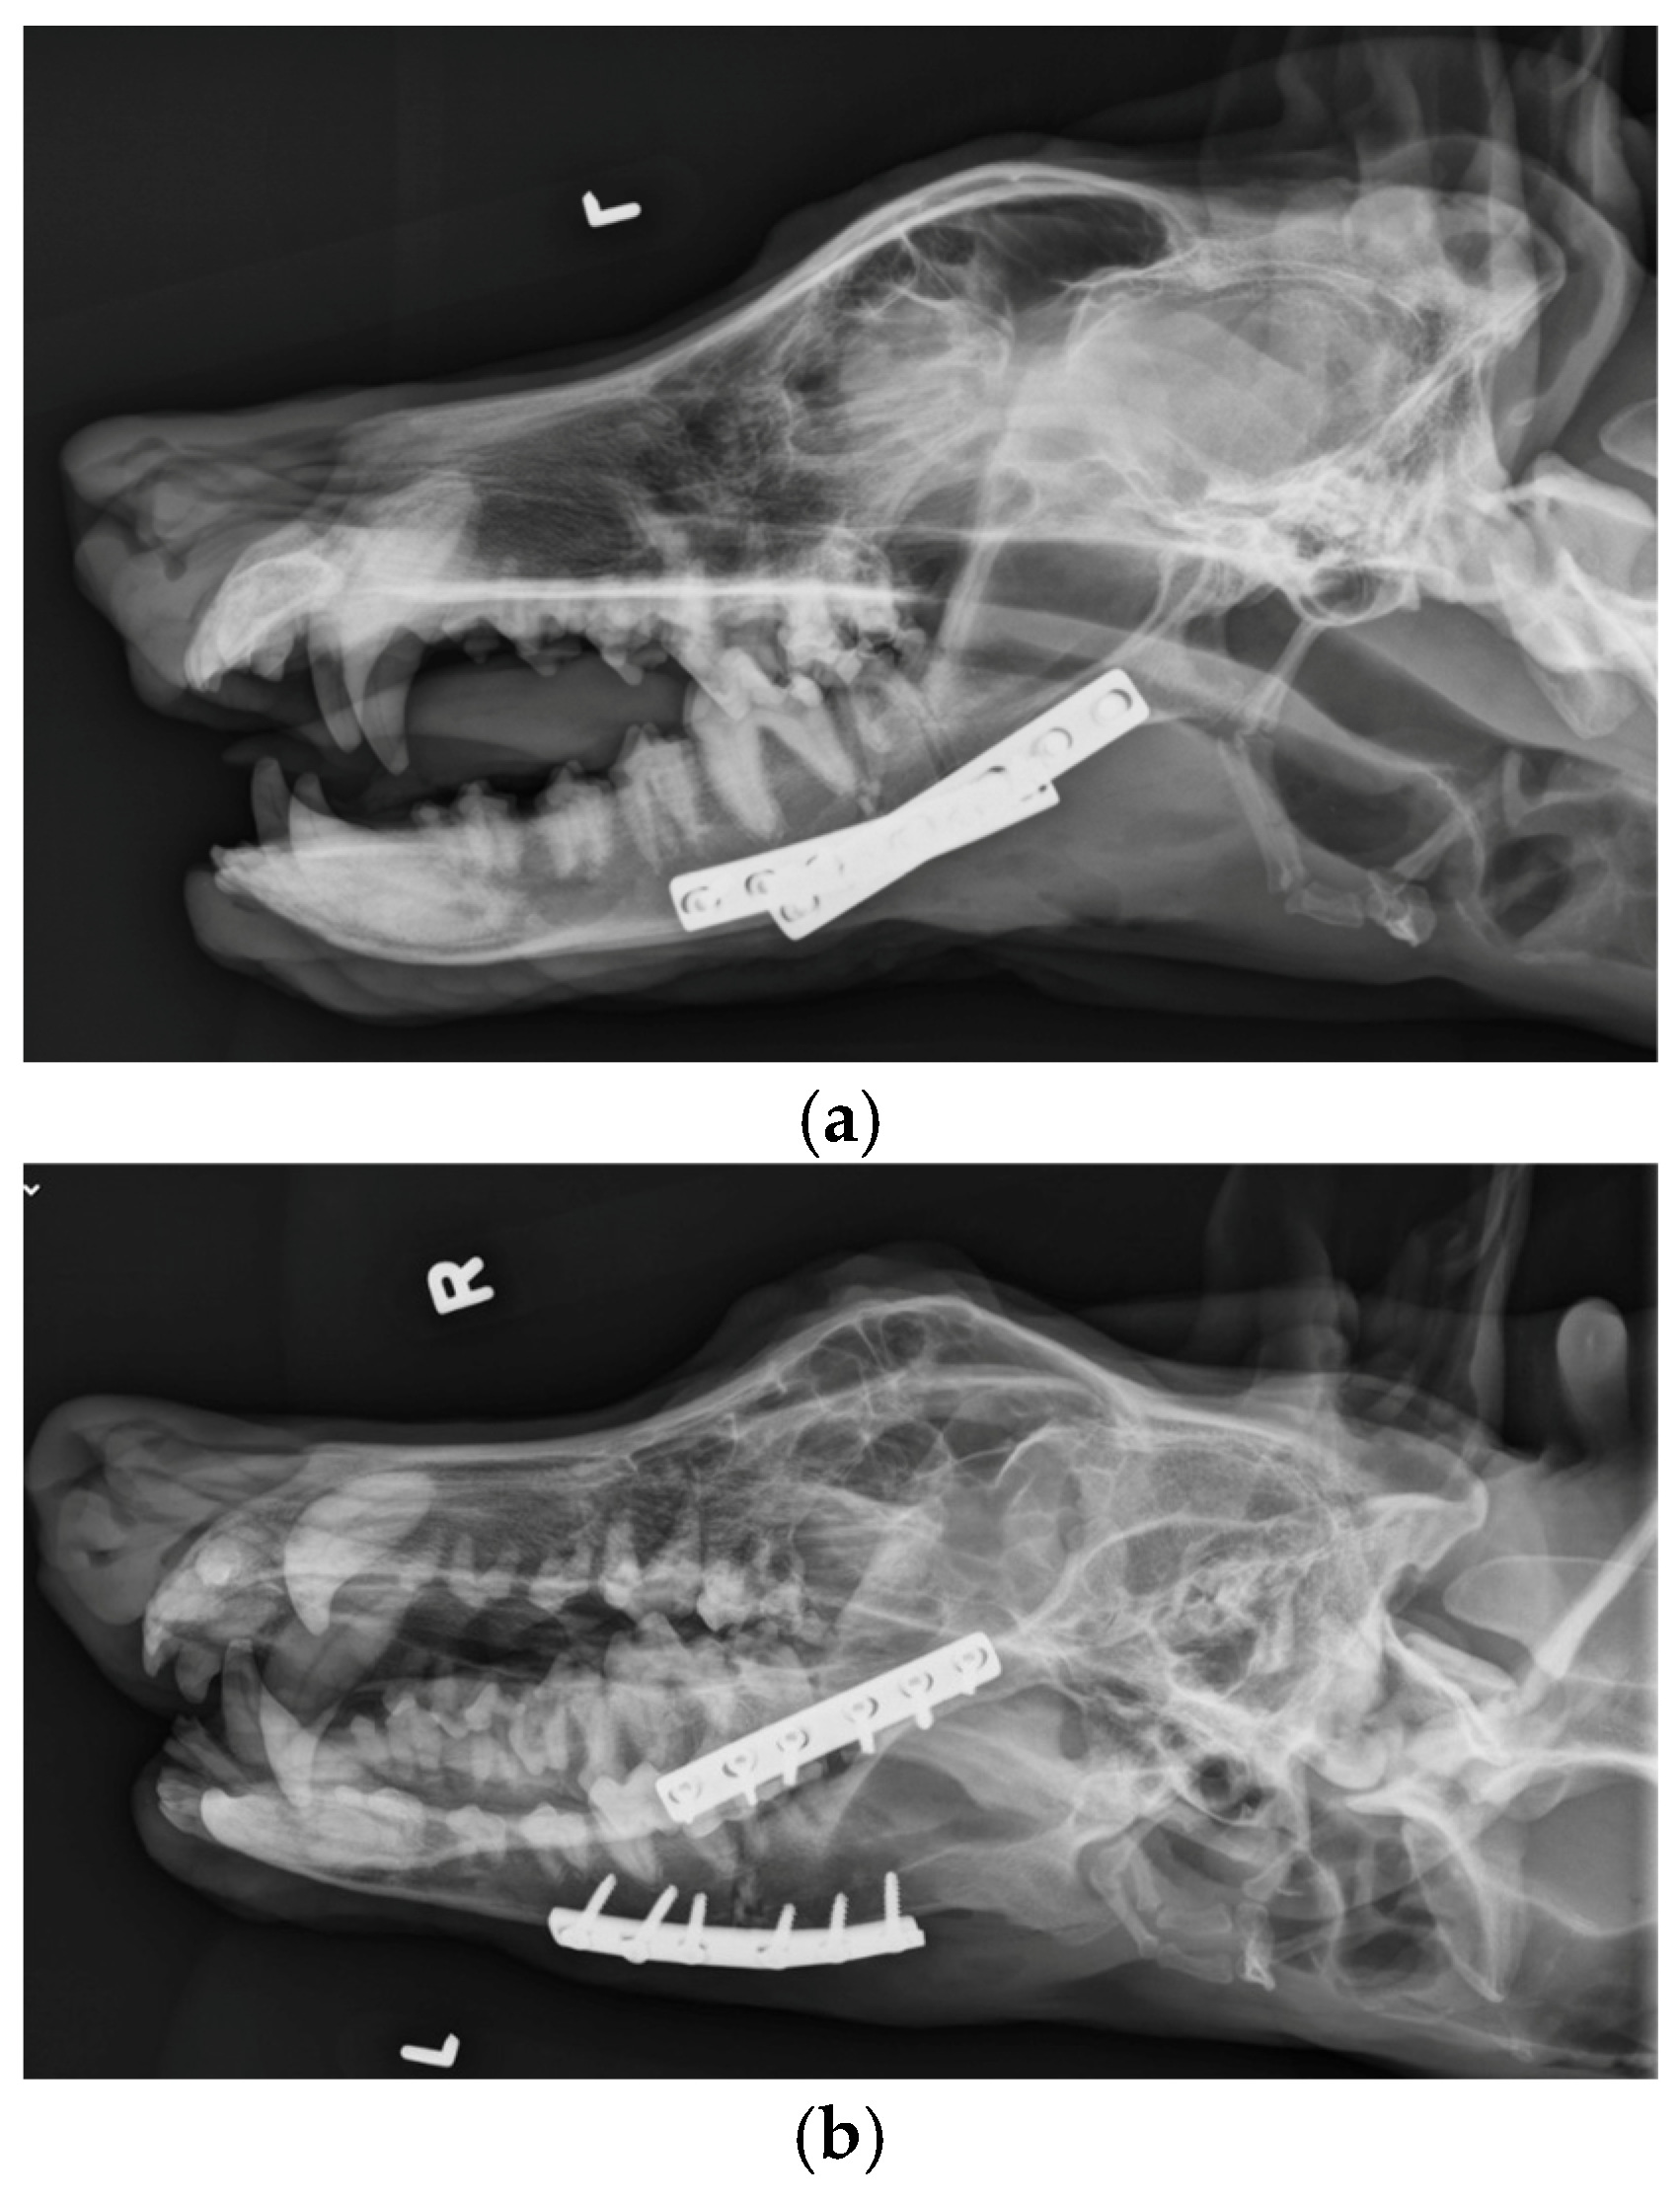

The patient was placed in dorsal recumbency and aseptically prepped from the level of the second tracheal ring to the rostral mandible and laterally to the ventral border of the zygomatic arch. An incision was made bilaterally over the caudal two-thirds of the ventral border of the mandibles and through the platysma muscle for exposure of the periosteum. The myloglossus and digastricus muscles were elevated from their attachments on the bone. A bilateral mandibular wedge ostectomy was performed, and bone plates and screws were used on either side to stabilize the mandibles to allow the mouth to remain permanently open to allow drinking, eating, and panting. (Figure 4 and Figure 5). The proposed ostectomy was outlined on the lateral and medial surfaces of each mandible. An oscillating bone saw was used to perform osteotomies along the medial and lateral aspects of each mandible, avoiding the mandibular canal. An osteotome was used to separate any remaining attachments between bones. The oral opening was visualized by a nonsterile assistant, and a spacer was placed to maintain an opening of approximately 3.5 cm. Bone was removed with the sagittal saw to create a closing wedge ostectomy to maintain the desired oral opening and maintain cortical contact of the mandible. Six-hole, 3.5 mm dynamic compression plates were placed on the ventrolateral aspect of the right and left mandibles with self-tapping, cortical screws to oppose the ostectomy sites, taking care to avoid tooth roots. Cancellous bone from the removed bone wedges was placed at the ostectomy lines. A minor operative complication was left mandibular artery trauma with hemorrhage that was controlled with bone wax. The post-operative radiographs confirmed both reduction and stabilization of the mandibular ramus bilaterally by means of the two plates. The tooth roots were avoided with screw placement (Figure 5 and Figure 6). The 3.5 cm opening was maintained between the upper and lower incisors postoperatively (Figure 7).

Figure 4.

A surgical incision was made on either side of the mandibles and a bilateral mandibular wedge ostectomy was performed using an oscillating bone saw 2 cm rostral to the border of the ventral ramus.

Figure 5.

A 6-hole, 3.5 mm compression plate was placed on the lateral aspect of each mandibular body.

Figure 6.

(a). Lateral. (b). Right dorsal-left ventral oblique. (c). Left dorsal-right ventral oblique. (d). Ventrodorsal view demonstrating bone plates and screws applied to the mandibular ramus bilaterally.